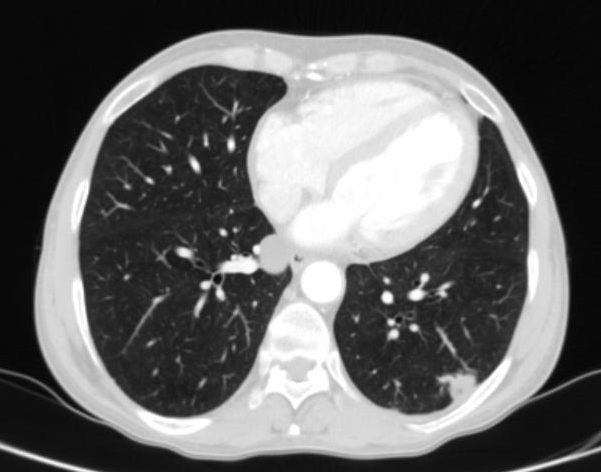

Do vaší ordinace vchází Milan Drahoš. Než se padesátiletý, velmi obézní muž dostane ode dveří k vámi nabízené židli, zadýchá se. Podle CT hrudníku, který si s sebou pacient přináší, má zvětšené uzliny v oblasti mediastina. Snímek odhaluje také mnohočetná ložiska plic. Není na co čekat, je třeba co nejrychleji zahájit léčbu. Ujmete se tohoto případu?